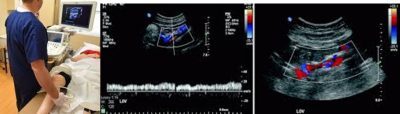

نعم ،بعد الفحص الاكلينيكي من جراح الاوعيه الدمويه، سوف تحتاج إلى فحص الأوردة في الساق بجهاز الدوبلر. هذا هو جهاز الفحص بالموجات فوق الصوتية الخاص بالاوعيه الدمويه .لا تحتاج لاي تحضير لهذه الاشعه (لا يجتاج الي صيام). يساعد هذا الفحص علي فحص أورده الساق (الاورده العميقه ،الاورده السطحيه الاساسيه ،الاورده السطحيه الفرعيه ،الاورده الثاقبه ،و الاورده العنكبوتيه).وهذا الاختبار يساعد على التأكد من أن عروقك مناسبة للعلاج بقسطره الليزر